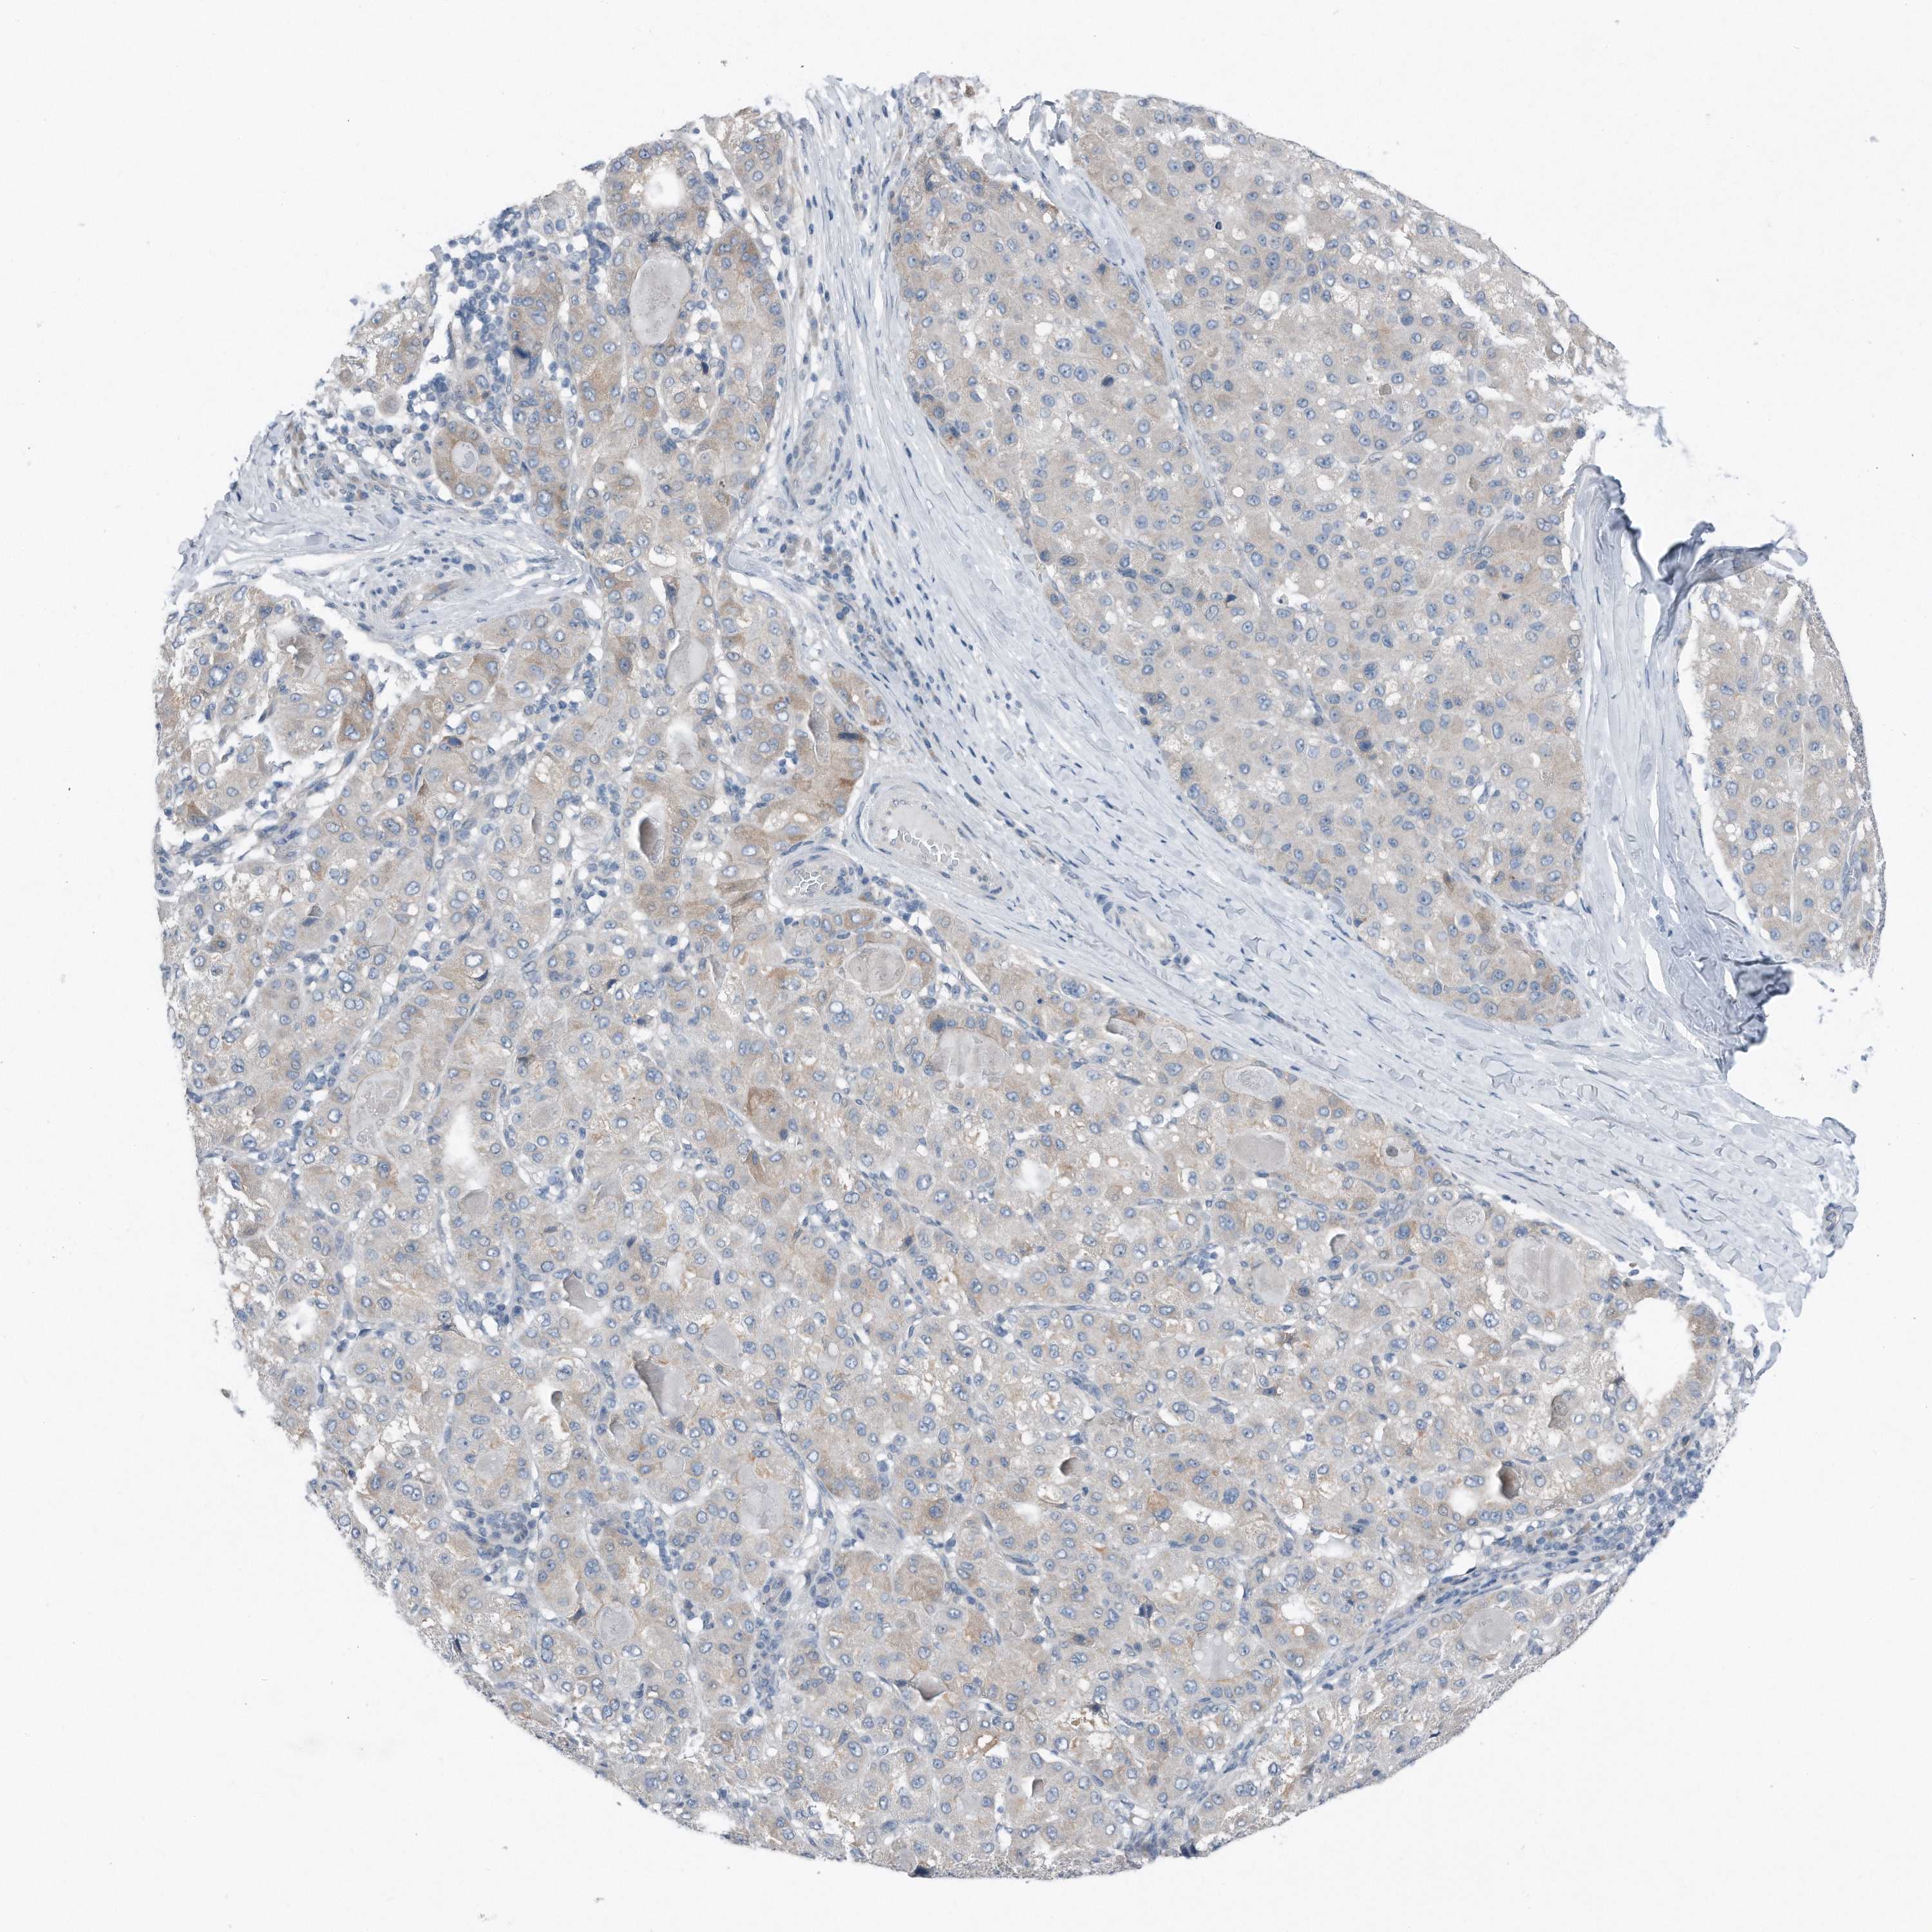

LIVER CANCER - Protein expressioni

A mouse-over function shows sample information and annotation data. Click on an image to view it in a full screen mode. Samples can be filtered based on level of antibody staining by selecting one or several of the following categories: high, medium, low and not detected. The assay and annotation is described here.

Note that samples used for immunohistochemistry by the Human Protein Atlas do not correspond to samples in the TCGA dataset.

Antibody stainingi

Antibody staining in the annotated cell types in the current human tissue is reported as not detected, low, medium, or high, based on conventional immunohistochemistry profiling in selected tissues. This score is based on the combination of the staining intensity and fraction of stained cells.

Each image is clickable and will lead to virtual microscopy that enables deeper exploration of all samples and also displays staining intensity scores, fraction scores and subcellular localization as well as patient and tissue information for each sample.

Antibody HPA030147

Staining

High

Medium

Low

Not detected

Intensity

Strong

Moderate

Weak

Negative

Quantity

>75%

75%-25%

<25%

None

Location

Nuclear

Cytoplasmic/membranous

Cytoplasmic/membranous,nuclear

Cholangiocarcinoma

Carcinoma, Hepatocellular, NOS